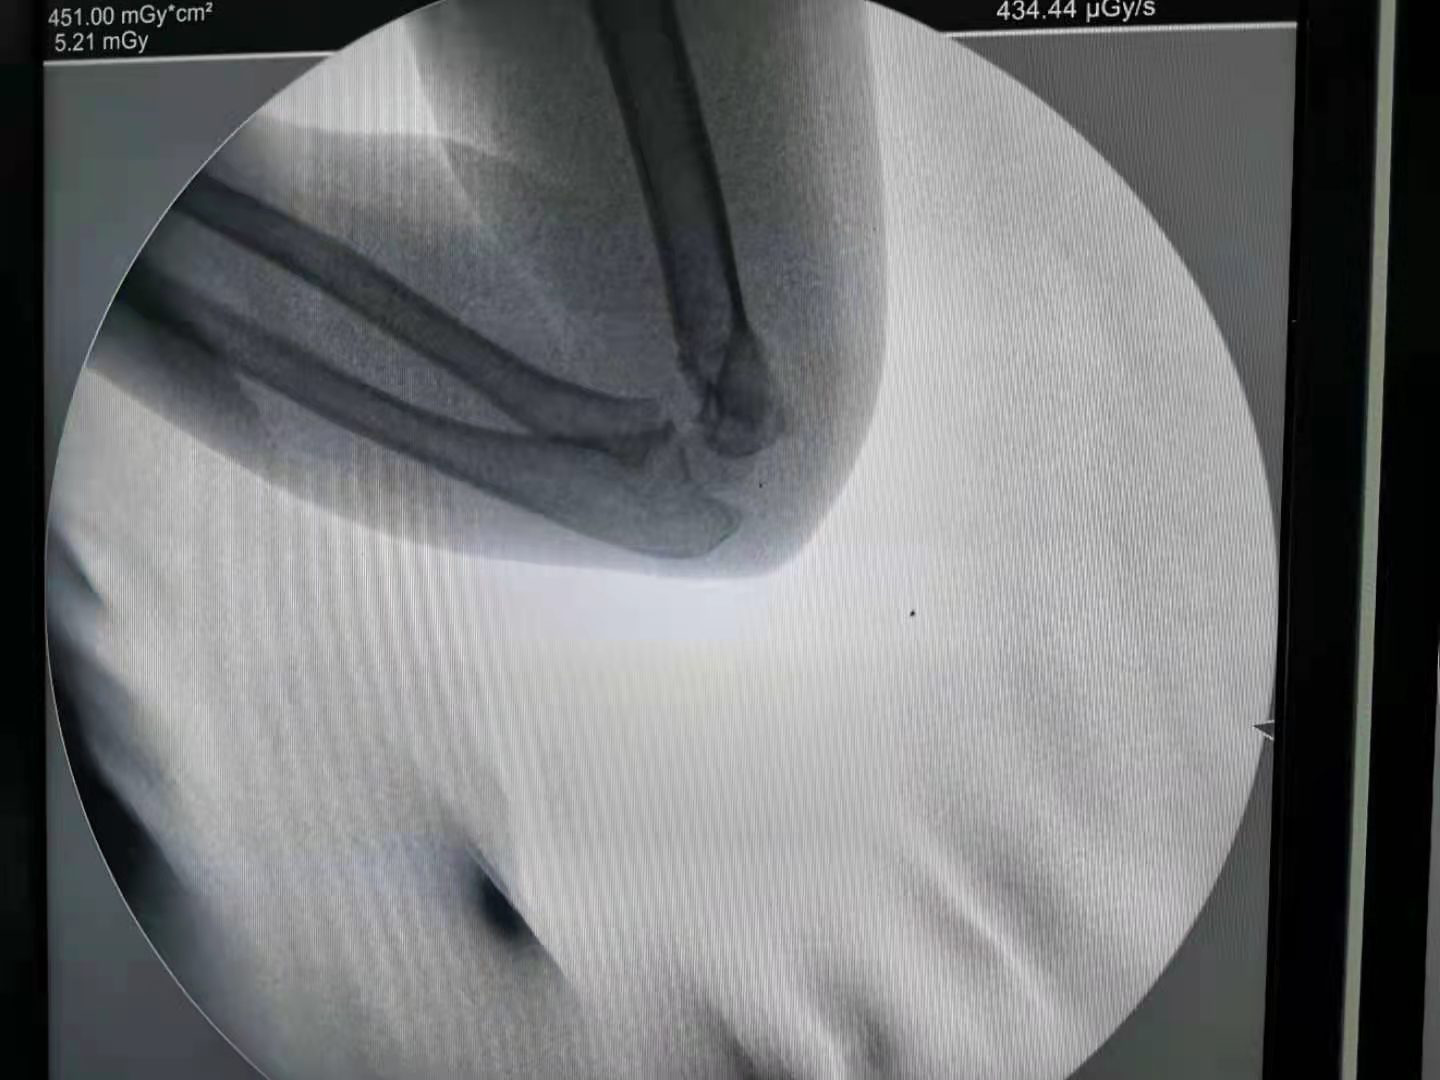

为了不断地满足患者的美观需求,同时医疗技术的不断提高,不需开刀不留瘢痕治疗儿童肱骨髁上骨折不再是梦。对于肱骨髁上骨折,我们的手术方法是“闭合复位经皮穿针固定”,是先进的微创手术方法,绝大多数不需要开刀,损伤很小,没有切口也不会留下瘢痕。只有非常少的情况下,例如开放性骨折或者骨折不可复位才可能需要做切开复位。